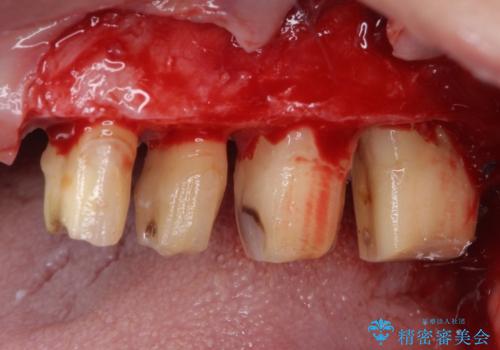

- 歯を磨く度に奥歯から出血するとのことで来院された患者様です。

歯周ポケット検査を行ったところ、6-8mmの歯周ポケットが散見され(正常では3mm以下)、歯周病治療が必要と判断されました。

仮歯に置き替え、歯周外科処置(APF、歯肉弁根尖側移動術)による歯周ポケット除去を行った後に、オールセラミッククラウンにて補綴することとしました。

歯周外科処置により歯周ポケットを除去することができ、クラウン装着後はブラッシング時の出血や歯肉の腫れが気にならなくなりました。